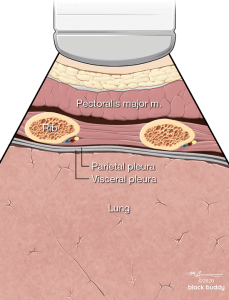

Anatomy

- The ribs will appear as convex hyperechoic lines with acoustic shadows.

- Located between the ribs are the hypoechoic intercostal muscles and the smooth, thin hyperechoic pleural line.

- These structures form the “bat sign”: the shadow of the ribs form the wings, while the area between the ribs represents the body.

Lung Sliding

- The pleural line is comprised of the parietal and visceral pleura, but will appear as a single, thin hyperechoic line.